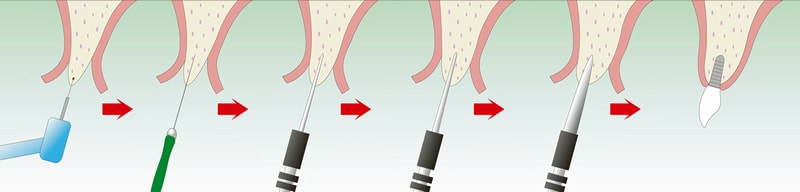

OAM(大口式)インプラントシステムを併用

OAMはドリルを使わず、インプラントを埋入する方法です。

骨をほとんど削らずに済むため、患者さんの身体的負担が少ないのが特徴です。

OAM(大口式)インプラントシステムを併用

OAMはドリルを使わず、インプラントを埋入する方法です。

骨をほとんど削らずに済むため、患者さんの身体的負担が少ないのが特徴です。